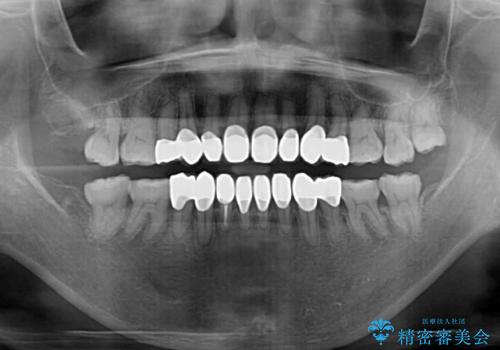

- 小さいころからの歯の変色と矯正治療の後戻りを気にして来院された患者様です。

気になる変色歯を仮歯に変え、その後歯列不正を矯正治療で改善し、最後にオールセラミッククラウンにて補綴治療することとしました。